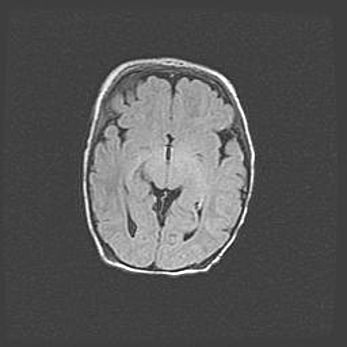

Сообщающаяся гидроцефалия. Кистозная энцефаломаляция головного мозга.

Возраст: 3 месяца 4 дня

Вес: 3100 г

Пол: женский

Окружность головы: 34 см

Срок гестации: 31 неделя

Кистозная энцефаломаляция головного мозга - одна из форм поражения головного мозга в детском возрасте. Характеризуется возникновением множественных и распространённых кист в коре, белом веществе и подкорковых образованиях головного мозга у плодов, новорождённых и детей раннего возраста. Развитие кистозной энцефаломаляции связано с внутриутробной асфиксией и гипотонией, родовой травмой, тромбозом синусов, пороками развития сосудов, инфекциями, сепсисом и другими причинами. Наиболее значимые инфекционные агенты: вирусы простого герпеса, цитомегалии, краснухи, токсоплазмы, энтеробактерии, золотистый стафилококк и другие.